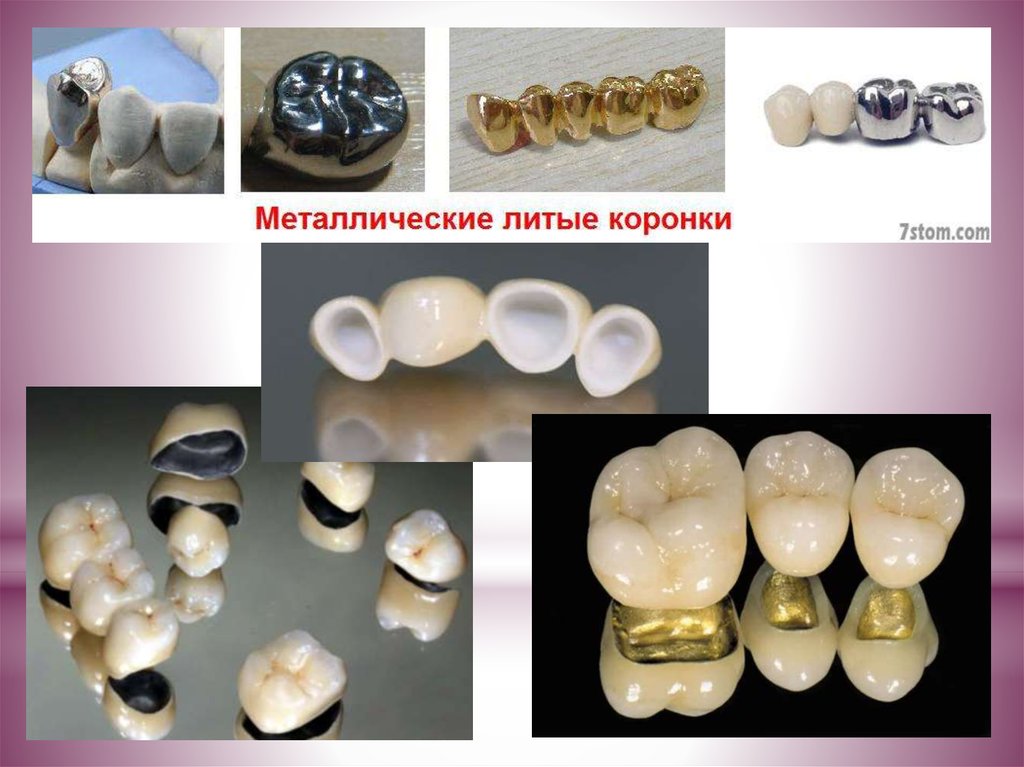

Разновидности зубных коронок и их особенности